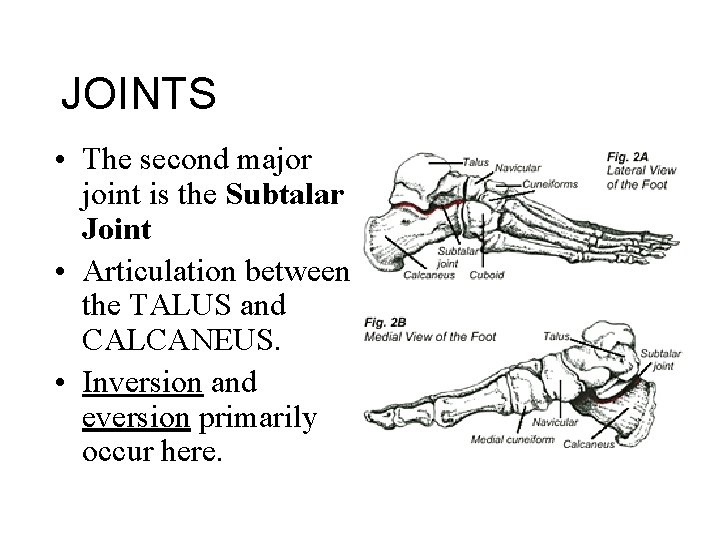

JOINTS • The second major joint is the Subtalar Joint • Articulation between the TALUS and CALCANEUS. • Inversion and eversion primarily occur here.